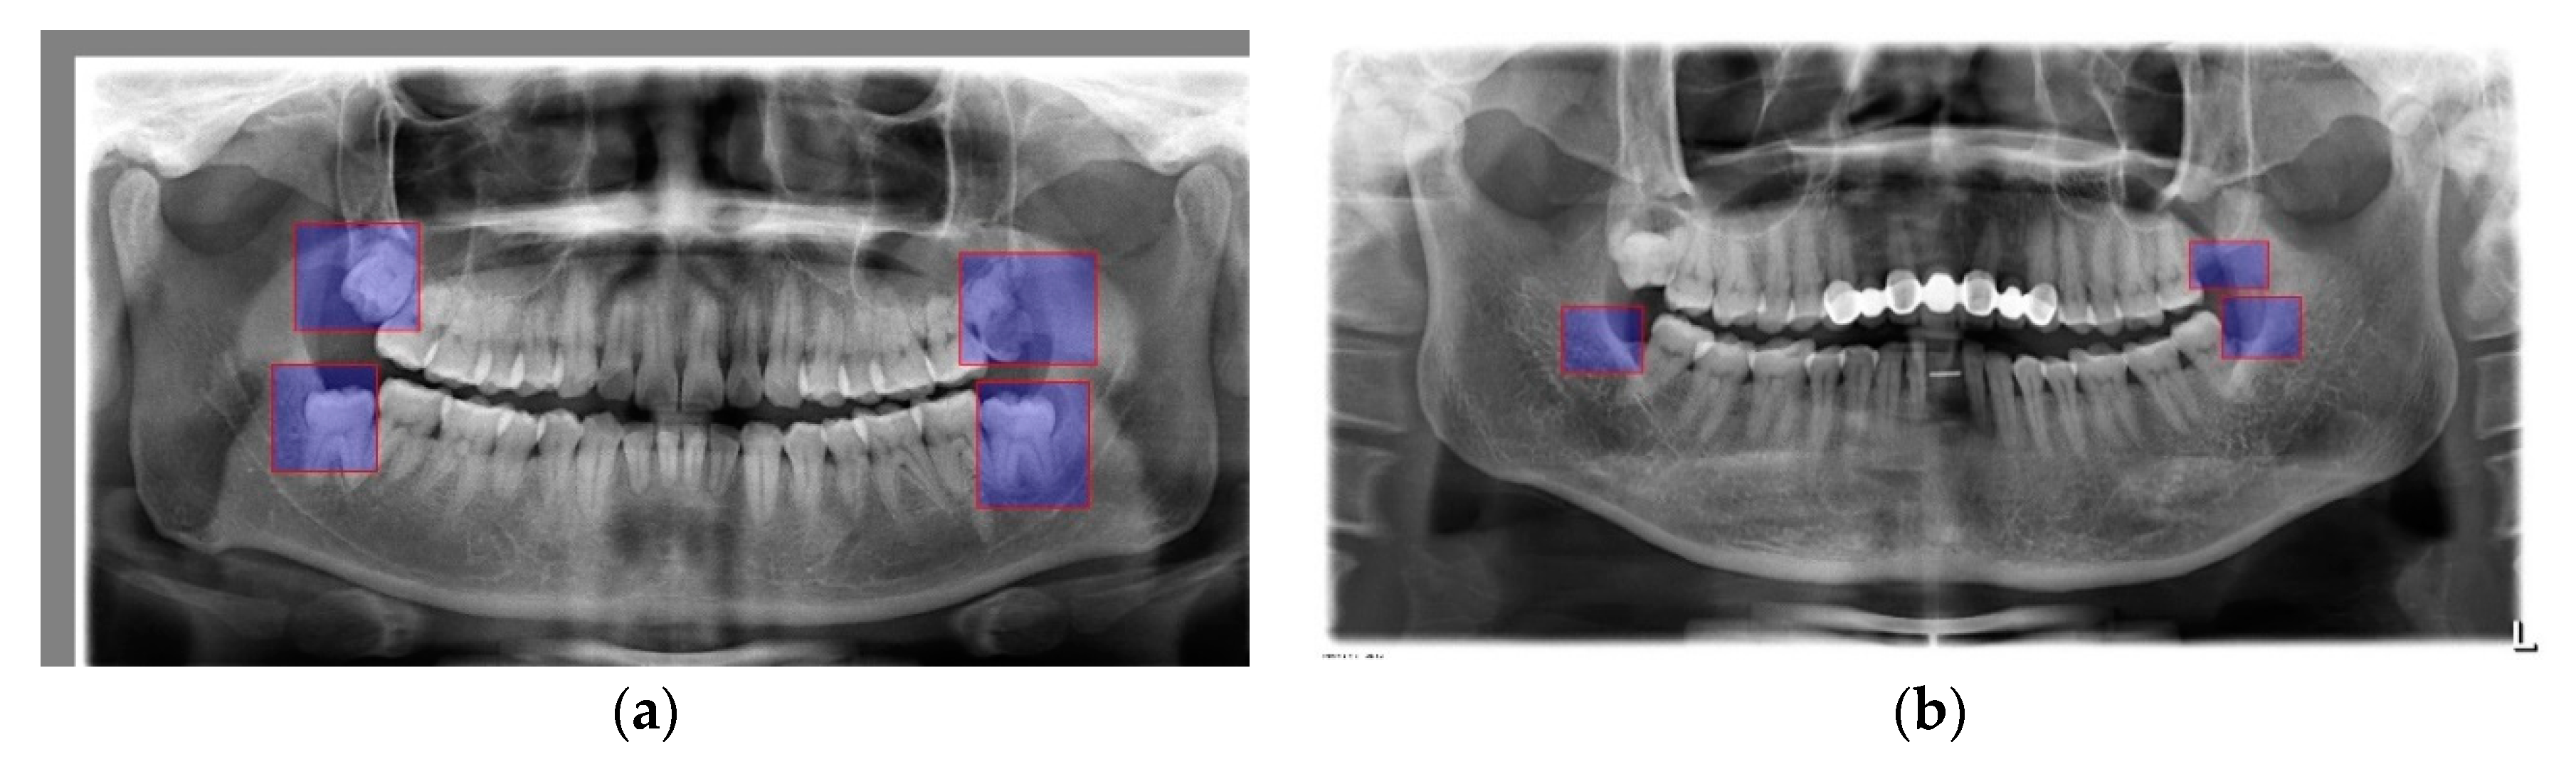

2.2.2. ROI Creation